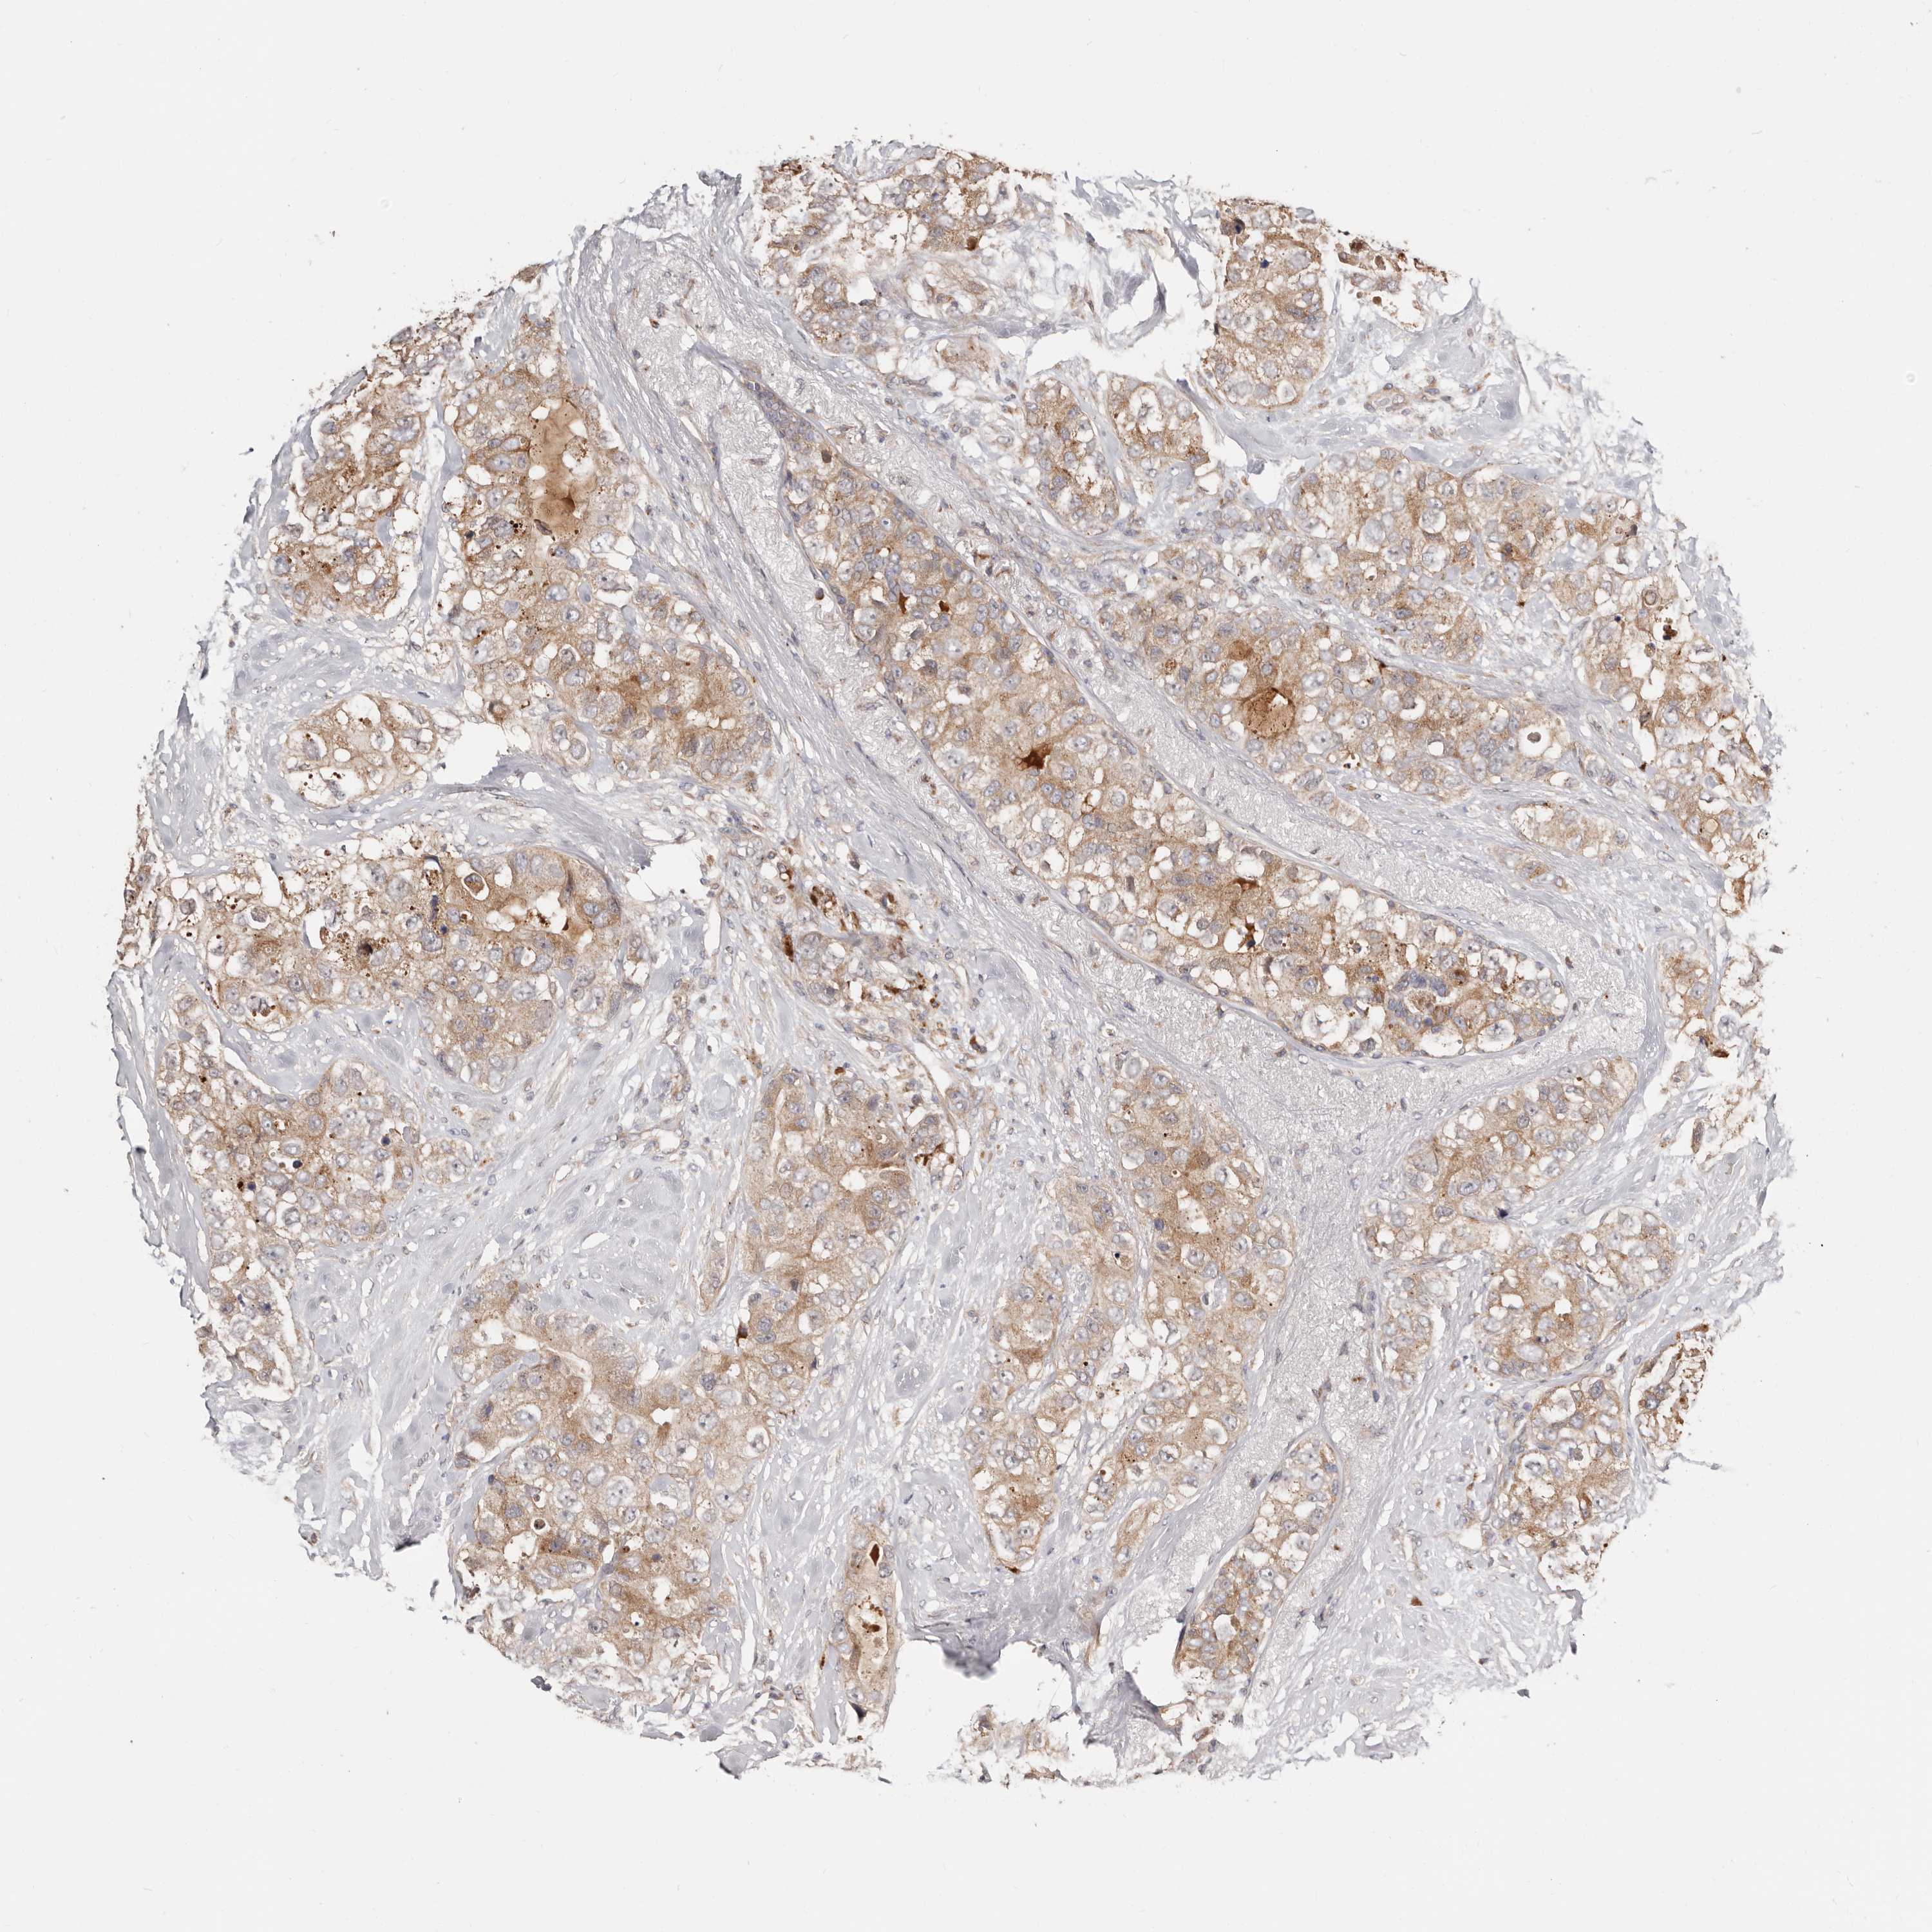

CANCER BREAST CANCER Show tissue menu

BRCA TCGA BRCA VALIDATION PROTEIN EXPRESSION